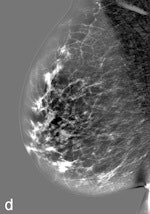

| Example of a subtle finding in a right-sided mediolateral oblique view, which was only reported by radiologists when using premium view (PV). A: Digitized prior. B: Tissue equalization (TE) processed image. C: PV processed image with the annotation. D: The resulting image of subtracting TE from PV. E: Thresholded version of D. White areas indicate that pixels in the PV image have relatively higher intensity than the related pixels in the TE image, whereas black areas indicate the opposite. In PV images, low-frequency trends are suppressed (no noticeable signal decrease in the breast edge in PV compared with TE), whereas higher-frequency structures are emphasized (e.g., glandular structures). All images courtesy of Wouter Veldkamp, PhD, Leiden University Medical Center. |

Another example of a finding in a left-sided craniocaudal view that was reported clearly more often by radiologists when using premium view (PV). A: Tissue equalization (TE) processed image. B: PV processed image with the annotation. C: Similar to image above, the resulting image of subtracting TE from PV. D: The thresholded version of C.For all six radiologists, perceived case suspiciousness -- defined as the highest probability of malignancy of all radiologist findings -- was higher using premium view optimization.